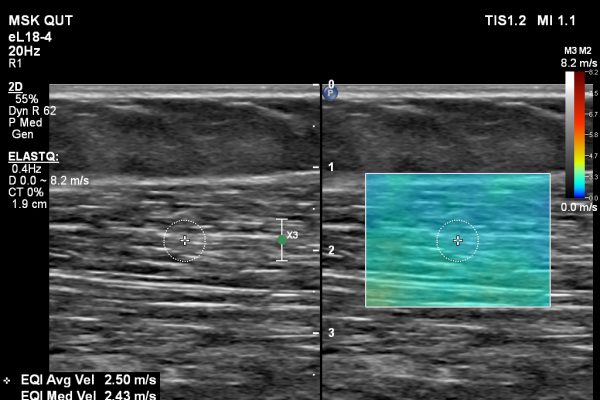

Shear Wave Elastography of Soft Tissues

Shear Wave Elastography (SWE) is an advanced ultrasound technology that can assess the biomechanical properties of tissue by measuring the velocity of shear waves travelling through the medium. At QUIQ…